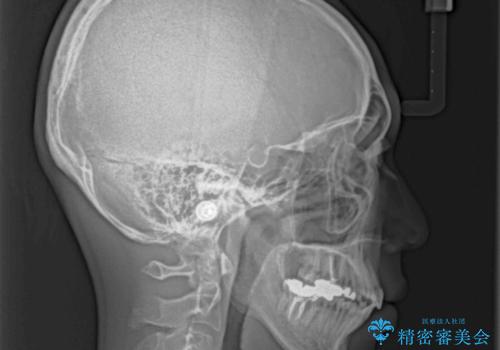

- 前歯のデコボコと八重歯、開咬を気にして来院された患者様です。

骨格的に下顎骨が上顎骨に対して後退位であったため、上顎の左右第一小臼歯を抜歯し、デコボコを改善するとともに開咬を改善していくこととしました。